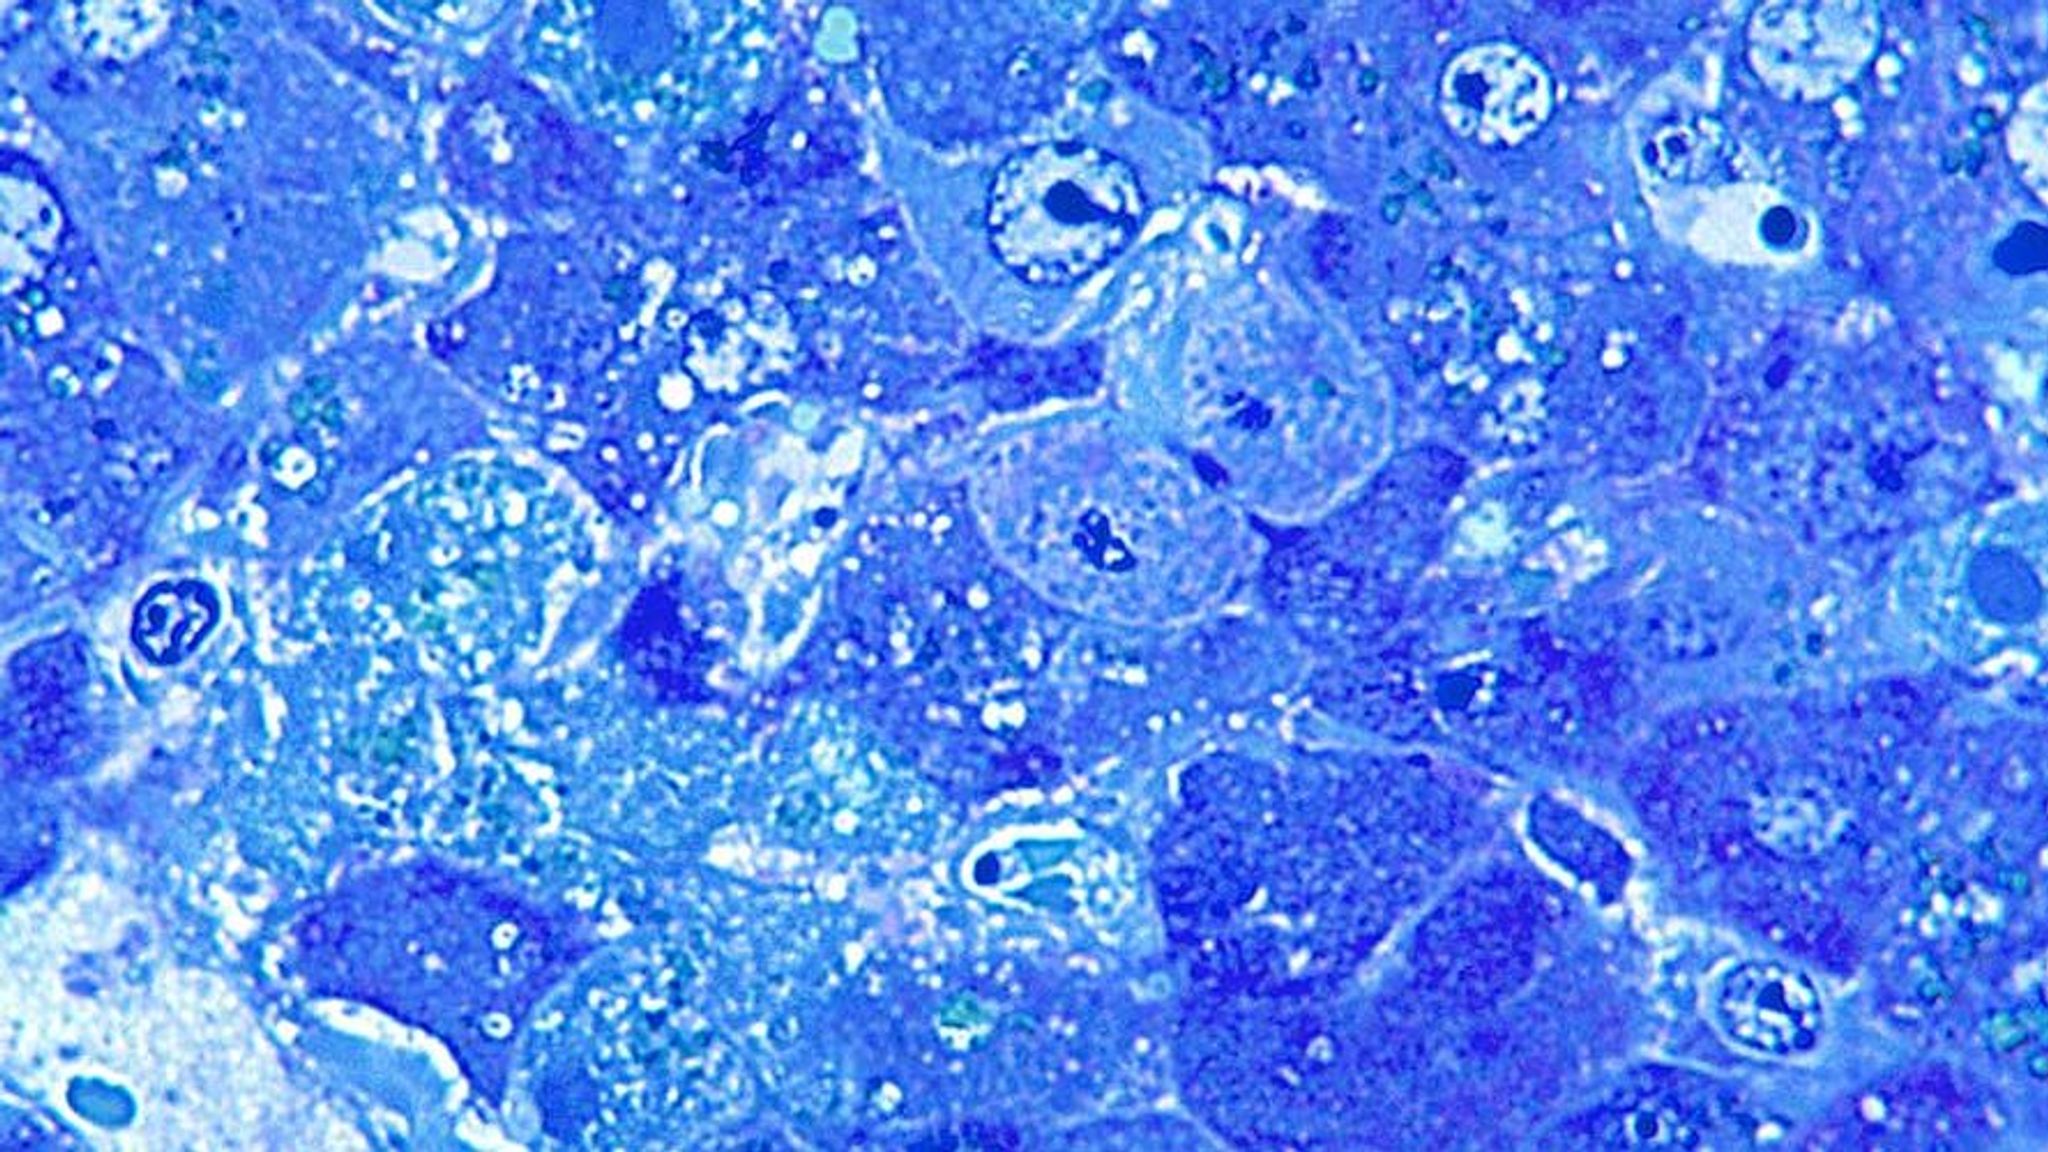

Lassa fever is caused by Lassa virus. Prior to these latest cases, there have been eight imported to the UK since 1980.

About 80% show no symptoms, while others experience a fever with aches and pains that can progress to headaches, vomiting and diarrhoea.

In severe cases there may be facial swelling, fluid in the lung cavity, bleeding from the mouth, nose, vagina or gastrointestinal tract and low blood pressure.

Deafness occurs in 25% of patients who survive the disease.